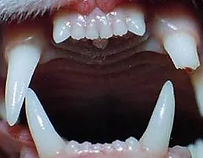

Complexo Gengivite-estomatite-faringite felina

Esta enfermidade autoimune também conhecida como gengivoestomatite crônica, causa ulcerações na gengivas, nas mucosas das bochechas e até na faringe.